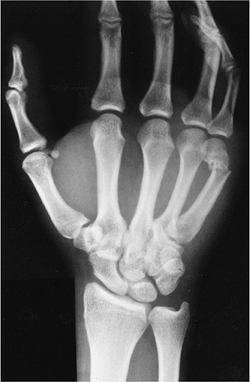

![]() |

|

FIGURE 9-23

The second to fifth metacarpals. There is laxity in the transverse metacarpal ligament between the fourth and fifth metacarpals that leads to shortening and rotation with oblique or spiral factures. There is more motion allowed at the fourth and fifth metacarpal bases. |